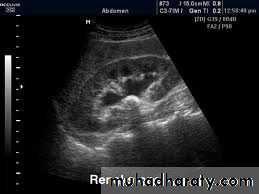

Ultrasound findings

1-Dilatation of the P.C.S. appears as multilocular fluid collection within central echo complex.-With more severe distention, dilated calyces appear as Multiple cysts but communicating with each other unlike true cysts.

2-Stones larger than 5 mm are easily seen on US but smaller ones may be missed.

-They produce intense echoes (hyperechoic) and cast acoustic shadows.

-Proximal and distal ureteric dilatation can be easily identified unlike mid-ureteric dilatation, and stones located in the middle third of the ureter are hard to be demonstrated unlike upper and lower ureteric stones (especially those lodged in the vesico-ureteric junction or pelvi -ureteric junction) which are easily identified by ultrasound.